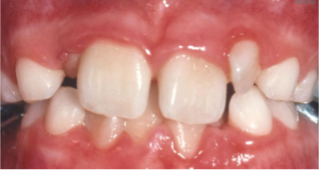

4/ Những dấu hiệu phụ huynh cần lưu ý

Nếu bé có các biểu hiện sau, cha mẹ nên đưa trẻ đi khám sớm:

- Khớp cắn ngược (răng dưới chìa ra trước)

- Khớp cắn hở (khi cắn lại vẫn hở khe giữa răng trước)

- Hàm hẹp, răng mọc chen chúc rõ rệt

Nguồn: Myfaceology

Nguồn: sarkissiandds

Nguồn: kidsdentalonline